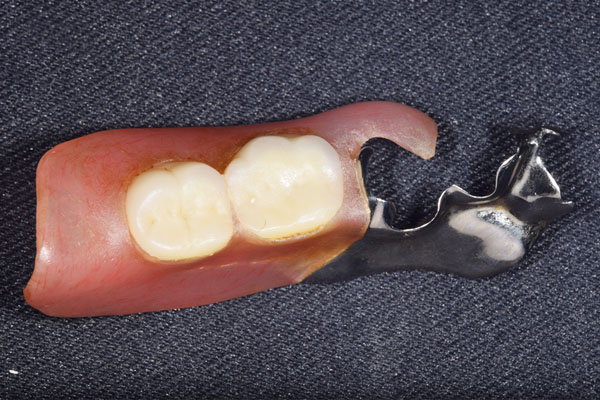

ケース5(金属使用 部分床義歯)

入れ歯をなくしてしまったので、あたらしく作りたい患者様です。

お口に入っている状態です。嘔吐反射が強かったため、うわあごの部分をくり抜いて作っています。

そのためにはしっかり歯に維持力をかける事、歯茎の部分に圧をかけるため、金属をつかって入れ歯を作成しました。

年齢 80代・女性

主訴 入れ歯をなくしたのであたらしくつくりたい。

治療期間 1ヶ月

治療費 義歯:330,000円(税込)

治療方針 以前作った入れ歯は気に入っていたが無くしてしまったとのことで、作り直しました。

上には残っている歯がありますが、入れ歯がない状態が続くと、歯へのダメージが強いことが考えられましたので、急ピッチで作っていくことにしました。

治療内容 入れ歯をつくるための前処置はとくに必要なかったため、すぐに入れ歯を作成していきます。

嘔吐反射が強く、普通の上顎の入れ歯を入れた時の違和感が強いため、口蓋部をくり抜いてつくっていきました。

そのため、歯や粘膜に維持負担を強くかけるため、金属を使用していくことにしました。

患者さんのお話をきいていると、前の入れ歯もそういう入れ歯をつくっていたとのことでした。

特記事項 入れ歯は完成してからがスタートです。入れ歯が歯ぐきにこすれて痛みが出る事が多いです。

今回の様な入れ歯ではそういう事が必ずと言っていいほどでます。

そのため、しっかり痛みをとるために入れ歯を調整して、患者さんに合わせた入れ歯にカスタマイズして完成になります。